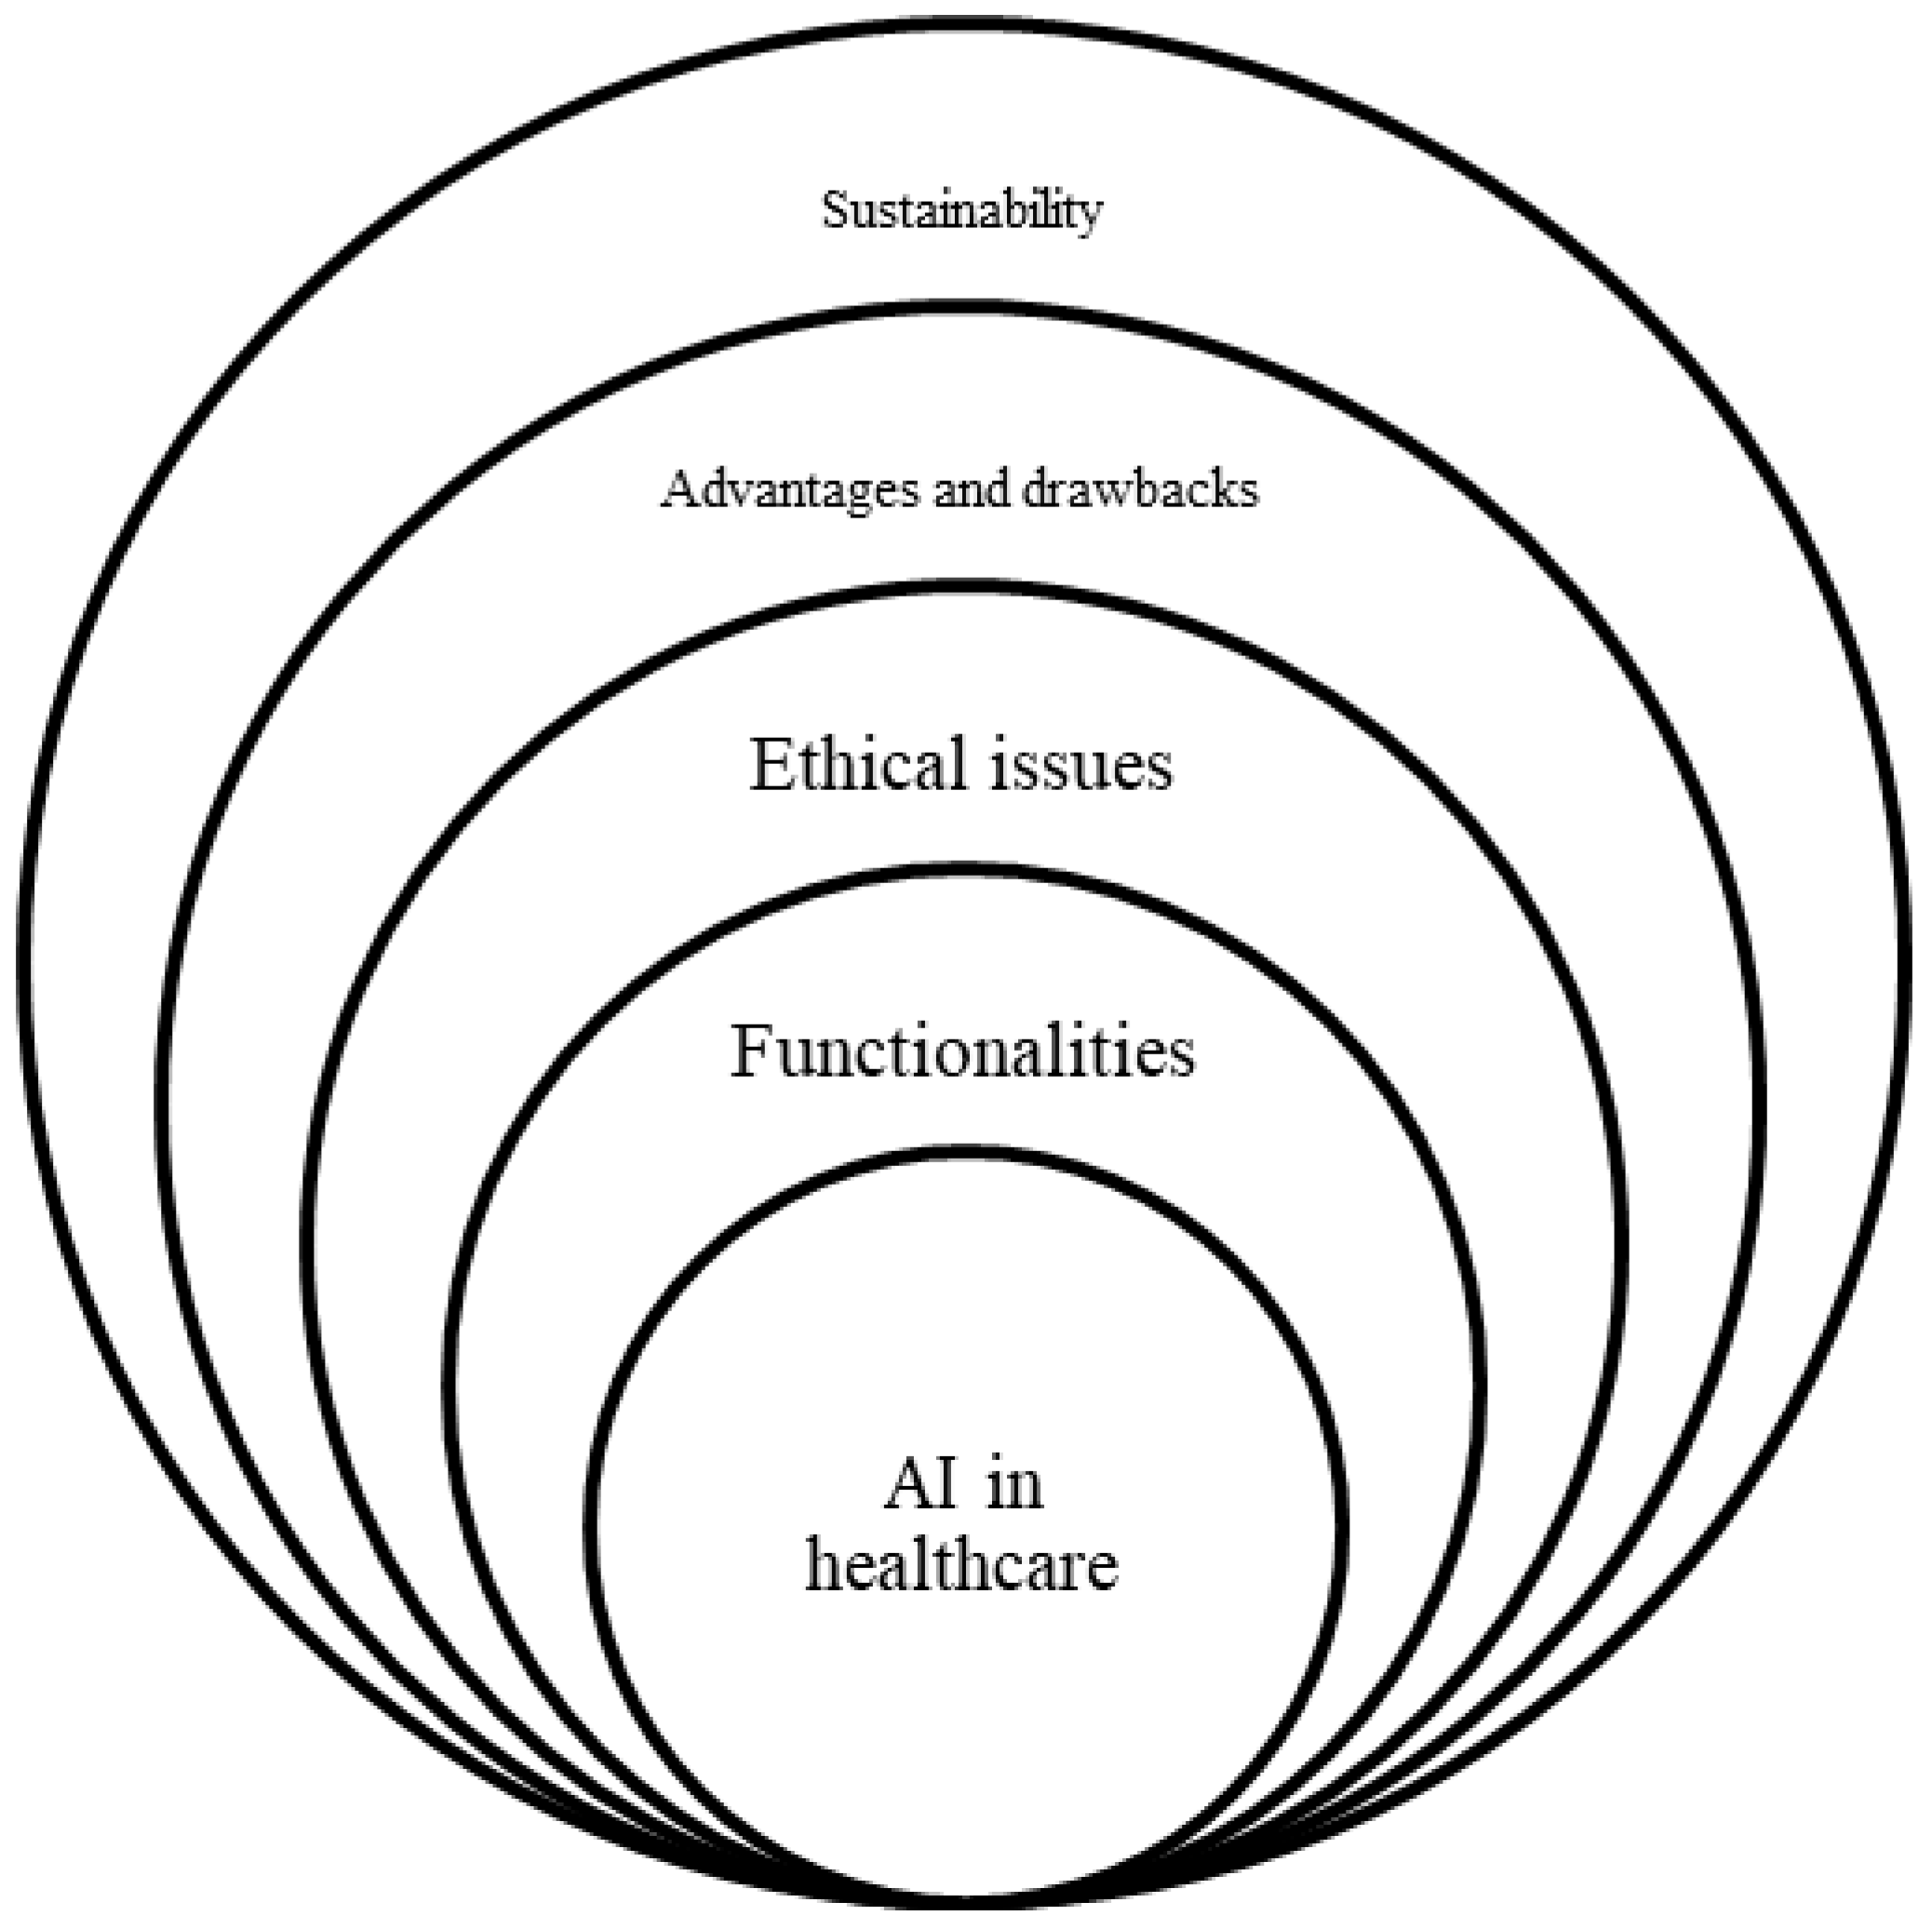

3. Classification Framework for Analysis